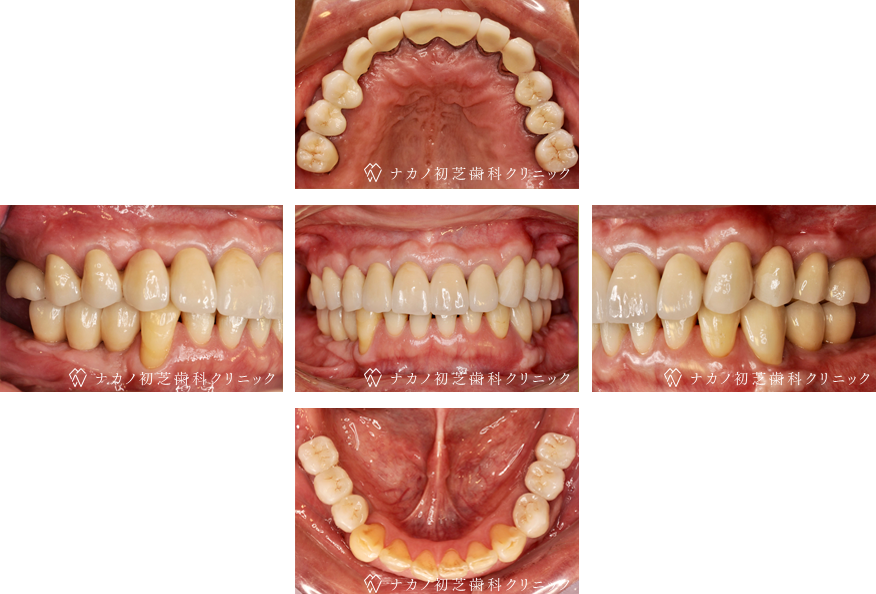

インプラント・13本 (60代女性)

BEFORE

AFTER

年齢 60代女性

治療内容 インプラント治療13本(骨造成の併用)

インプラント治療とは、歯を抜いた所にチタン製の人工歯根を埋入し、その上に歯を入れる方法です。骨を増やすことで、より審美的に治療が出来ました。費用 1本 400,000円(税込 440,000円)

リスク・副作用

腫れ・疼痛・違和感を感じるなどの症状を生じることがあります。